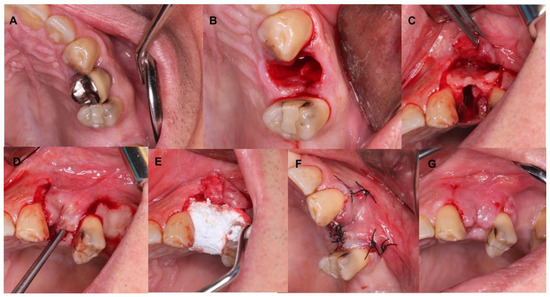

4.1. Patient No. 1

4.2. Patient No. 2

4.3. Patient No. 3

4.4. Patient No.4

4.5. Patient No.5

4.6. Patient No.6

| Patient Gender Age | Medical History of Interest [Toxic Habits] Type of Surgery | Closure by First Intention [Collagen Sponge] | I.M. | I. C. | Healing | Early Postoperative Complications | Late Postoperative Complications |

|---|---|---|---|---|---|---|---|

| 1 F 63 | NO [Tobacco: 2 cig/day] Horizontal Guided Bone Regeneration | Yes [No] | G | No | G | No | No |

| 2 M 52 | NO [-] Alveolar ridge preservation | No [Yes] | G | No | M | Graft loss and self-limited alveolitis | No |

| 3 M 61 | NO [-] Alveolar ridge preservation | Yes [No] | G | No | G | No | No osseointegration of the implant, replacement in 3 months, without problems and with good stability |

| 4 F 46 | NO [-] Alveolar ridge preservation | No [Yes] | G | No | M | Graft loss and self-limited alveolitis | No |

| 5 M 64 | NO [-] Sinus lift with lateral window | Yes [No] | G | No | G | No | No |

| 6 M 46 | NO [-] Sinus lift with lateral window | Yes [No] | G | No | G | No | No |